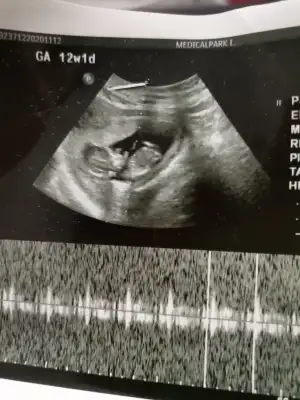

Eklentiler

• IMG_20201211_205625.webp

IMG_20201211_205625.webp

20,7 KB · Görüntüleme: 38

• IMG_20201211_205641.webp

IMG_20201211_205641.webp

25,1 KB · Görüntüleme: 34

• IMG_20201211_205702.webp

IMG_20201211_205702.webp

21,2 KB · Görüntüleme: 31

• Screenshot_2020-12-11-20-23-12-06.webp

Screenshot_2020-12-11-20-23-12-06.webp

22,1 KB · Görüntüleme: 53

Evet regl dönem bakınca 8 hafta doktor 9+3 dedi.

Teşekkürler bu ay sonu gibi çağırdı doktor 2.tarama yapıcak tekrar alırım ultrason buraya yüklerim.

13 hafta ya girmiş olucaz daha net olur o zaman çok teşekkür ederim sağolun